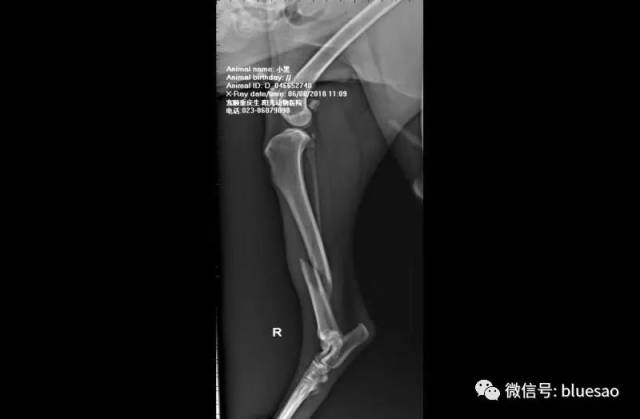

【病例分享】"小黑侠"胫骨长斜骨折,prcl锁定系统临床